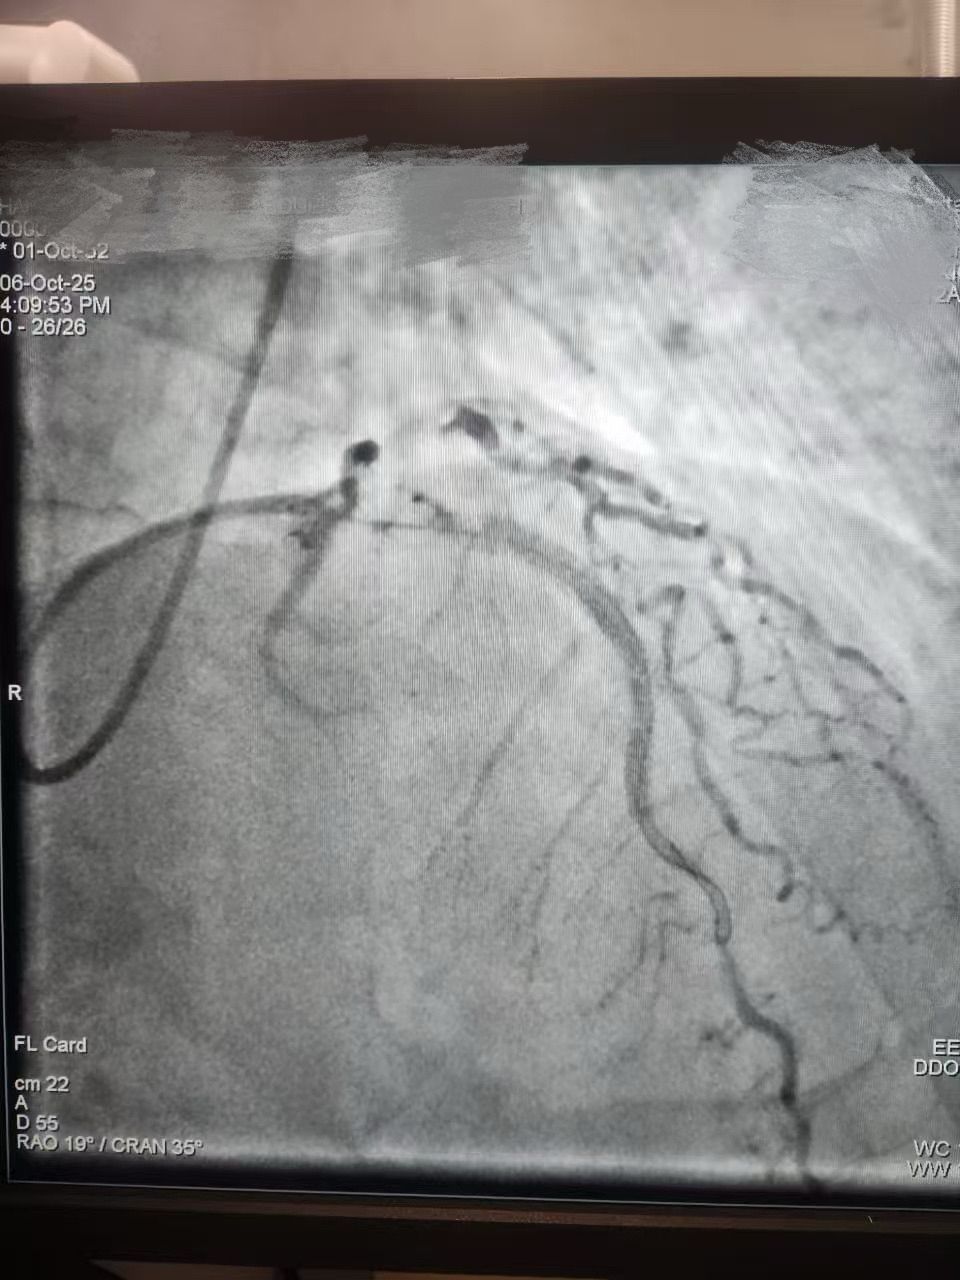

We are proud to share a successful clinical case from HMS Mirdif Hospital, UAE, where Dr. Mohamed Houcem Amiour and his exceptional Cath Lab team — Ambily Mathew, Aswathy S Babu, Geethanjali Rema Suresh, and Mathew Philip — successfully performed a PTCA to the LAD using Lepu Medical's Vesscrack Coronary IVL Balloon System.

To achieve optimal lesion preparation and stent expansion, the team skillfully combined Rotablator with Lepu's IVL, ensuring precise and effective calcium modification.